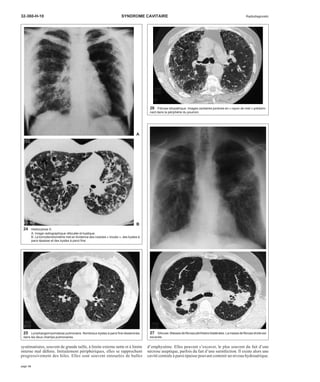

19 Métastases d’un cancer épidermoïde. Les excavations sont apparues sous

chimiothérapie.

20 Maladie de Hodgkin. Adénopathies médiastinales bilatérales et lésions pulmo-naires

excavées.

Métastases [27]

Les métastases pulmonaires sont plus rarement excavées que les cancers

primitifs. Toutes les tumeurs peuvent être en cause, mais plus

particulièrement les épithéliomas malpighiens (fig 19), en particulier

otorhinolaryngologiques (ORL) chez l’homme et génitaux chez la

femme. Les métastases excavées, et plus particulièrement les métastases

de sarcome, peuvent être responsables d’un pneumothorax par rupture

d’un nodule excavé sous-pleural. La cavitation peut être favorisée par la

chimiothérapie [76]. Les métastases excavées ont généralement une paroi

épaisse, mais une paroi fine et régulière est parfois observée dans les

métastases de sarcome.

Autres tumeurs

Des excavations ont été rapportées dans les lymphomes en particulier

hodgkiniens (fig 20) [57, 68], parfois non hodgkiniens [3] primitifs ou